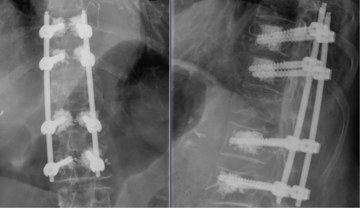

Hintere Stabilisierung eines Bruches des 12. Brustwirbelkörpers mit zementierten Schrauben und in minimalinvasiver Technik bei Osteoporose.